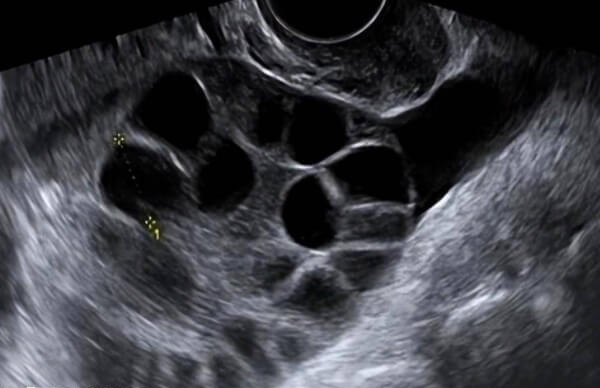

在做试管的过程中,促排卵进行打夜针的时候是非常关键的,而打夜针的目的是人为的给予绒毛膜促性腺激素,促进卵泡成熟,有利于医生定时取卵。打夜针后医生都会建议多休息,并注意少走路和避免提重物。

夜针的作用是促进卵泡成熟,通常在注射后36小时左右取卵。过度活动(如剧烈运动、频繁走动)可能刺激卵巢,导致卵泡提前破裂排出,影响取卵成功率。

促排过程中卵巢体积增大,在打夜针之后,女性体内的激素水平会进一步的升高,若这时活动过多或有提重物的情况下,可能使卵巢发生扭转,引发腹痛等紧急情况,影响后续治疗。